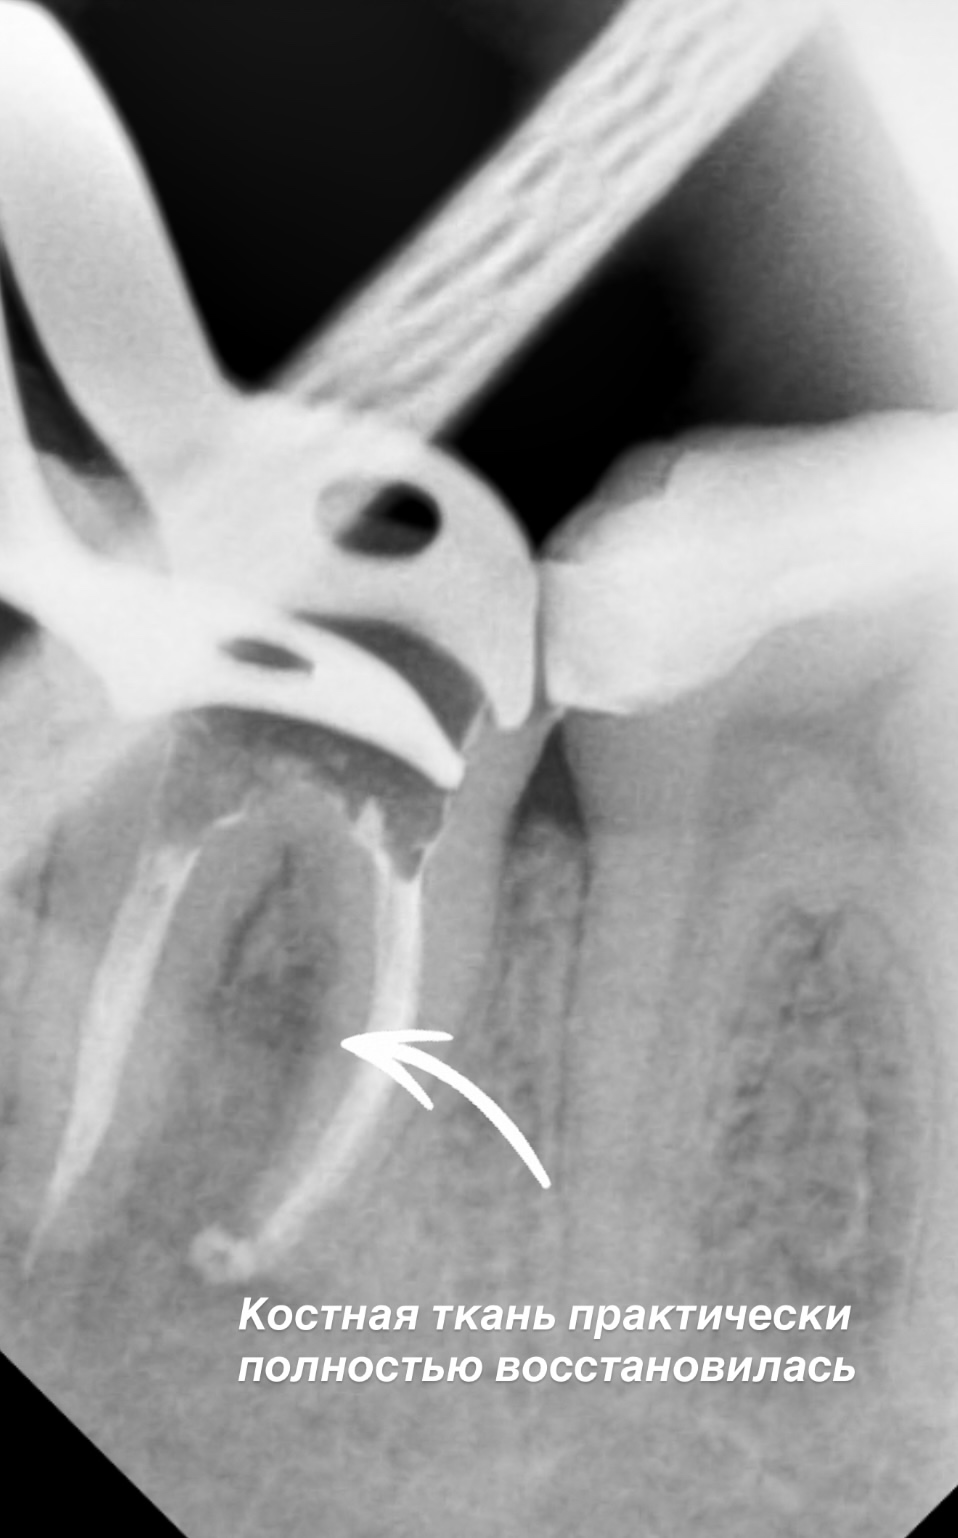

Сегодня расскажем о работе Морозовой Александры Сергеевны, которая смогла вернуть к жизни зуб, казалось бы, безнадежный. Пациент обратился к нам после консультации в другой клинике, где ему рекомендовали удалить инфицированный зуб. После тщательной диагностики по результатам компьютерной томографии, прицельным рентгенографияческим снимками и диагностическому препарированию под микроскопом, было решено зуб сохранять. Проведенное лечение корневых каналов под большим увеличением позволило тщательно и качественно очистить пораженные участки. После этого было выполнено пломбирование, и зуб был восстановлен и подготовлен под временную коронку для дальнейшего наблюдения.

Важно отметить, что при благоприятных условиях и положительной динамике состояния зуба через полгода временная коронка будет заменена на постоянную. Это еще раз подтверждает, что даже в самых трудных ситуациях всегда есть выход.